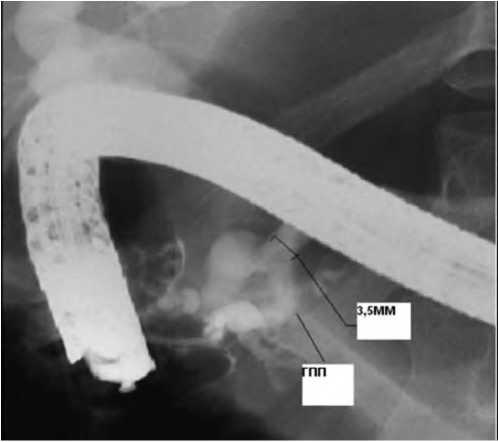

15.11.2010 г. выполнена эндоскопическая ретроградная панкреатикохолангиография: Вирсунгов проток в области тела расширен до 3,5 мм, ацинарные протоки не контрастируются. В области головки поджелудочной железы проток извит, деформирован, сужен от 1 до 2 мм. Выполнено эндопротезирование, стент 5Fr - 7см, Wilsopn-Cook. (рис.).

Рис. 1. Эндоскопическая ретроградная панкреатикохолангирграфия. Расширение главного панкреатического протока (ГПП) до 3,5 мм

23.12.2010 г. проведено репротезирование главного панкреатического протока стентом большего диаметра (7Fr - 7см). Через четыре месяца (04.2011) выполнено извлечение стента из панкреатического протока. Послеоперационный период протекал без осложнений.